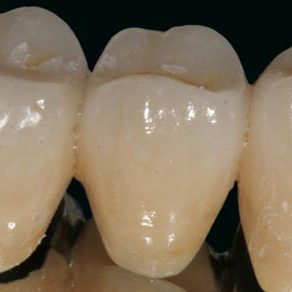

ApprofondisciCONSERVATIVA

La Terapia Conservativa si occupa della sostituzione di parti di dente di dimensioni contenute, compromesse da carie o fratture. Vengono utilizzati materiali particolarmente sofisticati che consentono la fabbricazione del restauro direttamente nel cavo orale.